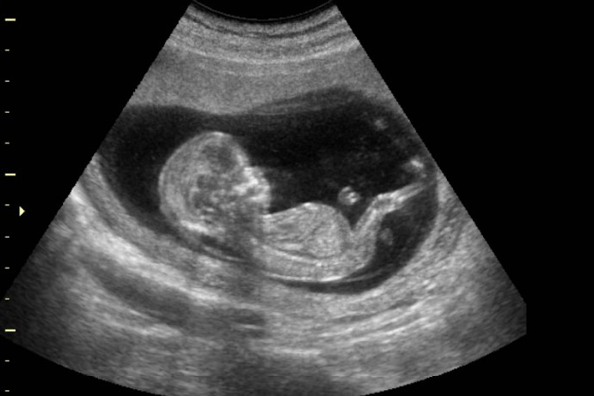

La primera ecografía que se realiza durante el embarazo se conoce como ecografía del primer trimestre. Esta prueba se realiza entre las semanas 10 y 14 de gestación y tiene varios objetivos importantes. En primer lugar, se utiliza para confirmar el embarazo y determinar la edad gestacional exacta. También se utiliza para evaluar el crecimiento y desarrollo del feto, así como para detectar posibles anomalías estructurales.

La ecografía del primer trimestre también permite evaluar la ubicación del saco gestacional y la placenta, así como para detectar la presencia de múltiples embarazos. Además, se utiliza para medir el grosor del pliegue nucal, que es un indicador de riesgo de anomalías cromosómicas, como el síndrome de Down.

La siguiente ecografía recomendada durante el embarazo se realiza entre las semanas 16 y 18. Esta prueba tiene como objetivo evaluar el crecimiento y desarrollo del feto, así como detectar posibles anomalías estructurales. Durante esta ecografía, se pueden observar los órganos internos del feto, como el corazón, los pulmones, el estómago y los riñones.

Además, se pueden medir las extremidades y la cabeza del feto para evaluar su crecimiento. También se puede determinar el sexo del bebé si los padres desean saberlo. Esta ecografía es una oportunidad para ver a tu bebé en movimiento y obtener imágenes más detalladas de su desarrollo.